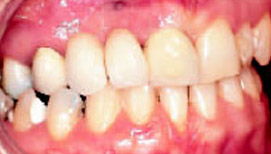

Эласто-Aligner особенно эффективен как основной лечебный аппарат при коррекции обратного резцового перекрытия и привычного смещения нижней челюсти (рис. 3-6). В этих случаях на Set-up изменяется положение только тех зубов, которые имеют неправильное положение. При этом необходимо обратить особое внимание на наклон нижних фронтальных зубов, которые за счет неправильного распределения жевательной нагрузки имеют небольшую протрузию.

Рис.3:Обратное резцовое перекрытие

Рис.4: Set-up делают только для тех зубов, которые переместить.

Рис.5: Через 3 дня после начала лечения

В процессе лечение в результате одновременного перемещения зубов – протрудирование верхних и ретрудирование нижних резцов – нормализация смыкания зубов достигается за очень короткое время. Даже при врожденной патологии достаточно обычного режима ношения аппарата - всего два часа днем и всю ночь.

Рис.6: Через 2 недели после начала лечения

Обратное резцовое перекрытие часто сочетается с мезиальным смещением нижней челюсти, при определении конструктивного прикуса нижнюю челюсть необходимо установить в ретро-положение. Кроме того, чтобы найти оптимальное положение зубов, необходимо обратить внимание на характер окклюзионных контактов.